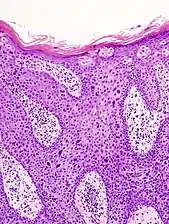

Characteristics

Histopathologically, the epidermis in SCC in situ (Bowen’s disease) will show hyperkeratosis and parakeratosis. There will also be marked acanthosis with elongation and thickening of the rete ridges. These changes will overly keratinocytic cells which are often highly atypical and may in fact have a more unusual appearance than invasive SCC. The atypia spans the full thickness of the epidermis, with the keratinocytes demonstrating intense mitotic activity, pleomorphism, and greatly enlarged nuclei. They will also show a loss of maturity and polarity, giving the epidermis a disordered or “windblown” appearance.

Two types of multinucleated cells may be seen: the first will present as a multinucleated giant cell, and the second will appear as a dyskeratotic cell engulfed in the cytoplasm of a keratinocyte. Occasionally, cells of the upper epidermis will undergo vacuolization, demonstrating an abundant and strongly eosinophilic cytoplasm. There may be a mild to moderate lymphohistiocytic infiltrate detected in the upper dermis.[33]

In situ disease

Bowen's disease is essentially equivalent to and used interchangeably with SCC in situ, when not having invaded through the basement membrane.[33] Depending on source, it is classified as precancerous[34] or SCC in situ (technically cancerous but non-invasive).[35][36] In SCC in situ (Bowen's disease), atypical squamous cells proliferate through the whole thickness of the epidermis.[33] The entire tumor is confined to the epidermis and does not invade into the dermis.[33] The cells are often highly atypical under the microscope, and may in fact look more unusual than the cells of some invasive squamous cell carcinomas.[33]

In invasive SCC, tumor cells infiltrate through the basement membrane. The infiltrate can be somewhat difficult to detect in the early stages of invasion: however, additional indicators such as full thickness epidermal atypia and the involvement of hair follicles can be used to facilitate the diagnosis. Later stages of invasion are characterized by the formation of nests of atypical tumor cells in the dermis, often with a corresponding inflammatory infiltrate.[33]